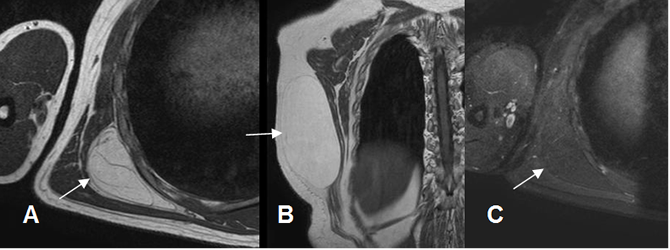

Fig 42. Lipoma.

A: RM axial en T1, B: RM coronal en T1 y C: RM axial en STIR. Lesión ovalada y de bordes definidos en la pared posterolateral de la reja costal, hiperintensa en T1 y que suprime en STIR, compatible con lipoma. Muestra capsula hipointensa y algunos septos delgados.